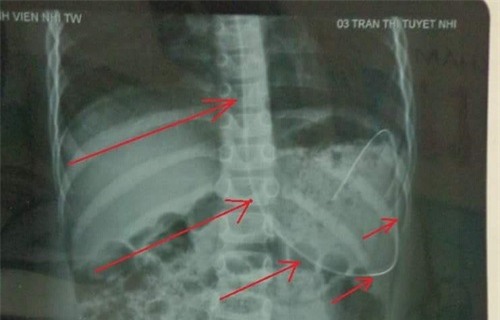

Khi phóng viên hỏi về tình trạng bệnh cụ thể của cháu Tuyết Nhi, anh Tiến nghẹn ngào: “Hiện cháu sức khỏe yếu quá không đủ sức phẫu thuật, vì thế bác sĩ khuyên cho cháu về quê điều trị bằng thuốc, một tuần sau đưa cháu ra viện tái khám”.

“Cùng với thời điểm cháu Nhi xuất hiện những biểu hiện nặng, vợ tôi sinh đôi hai cháu nhỏ và gia đình tôi về quê sinh sống. Cho đến thời gian gần đây, bệnh cháu Nhi ngày càng nặng, tôi đã đưa cháu ra bệnh viện tỉnh để thăm khám. Bệnh viện tỉnh đã chuyển thẳng cháu ra Bệnh viện Nhi Trung ương”, anh Tiến cho hay.

“Ngày 6/11 vừa rồi ra viện Nhi khám, nhận được kết quả tôi như gục ngã hoàn toàn, cháu giờ sức khỏe quá yếu không thể thực hiện được ca phẫu thuật, bác sĩ cho cháu về nhà điều trị bằng thuốc và chăm sóc nâng cao thể trạng rồi phẫu thuật sau.

Nhưng các bác sĩ cũng nói thẳng rằng việc phẫu thuật cho cháu cơ hội sẽ là 50/50, thậm chí là cháu sẽ không còn đi lại được nữa”, anh Tiến kể lại.